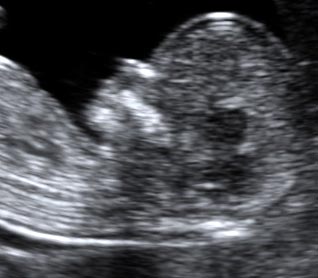

香港结构超声波照片

结构性超声波, 四维 香港, 四维结构性超声波 结构性超声波, 四维 结构性超声波, 四维 香港, 四维结构性超声波 结构性超声波, 四维 香港, 四维结构性超声波 结构性超声波, 四维 结构性超声波, 四维 结构性超声波, 四维 香港, 四维结构性超声波 结构性超声波, 四维 香港, 四维结构性超声波 结构性超声波, 四维 结构性超声波, 四维